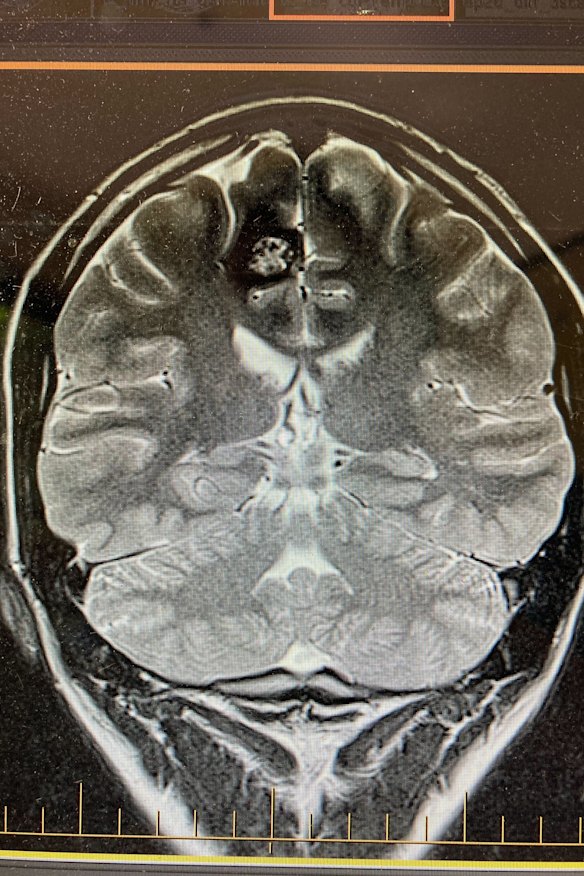

A scan of Angus Thomson’s brain showing the cavernoma at top left, which was causing his hand to shake uncontrollably.

The tremors had begun in my hand; the ring and the little finger, twitching as if pulled by invisible strings. When they progressed into full arm convulsions, an MRI confirmed the culprit: a non-cancerous, raspberry-sized formation of blood vessels called a cavernoma. Within two weeks I had an appointment with one of Drummond’s neurosurgical colleagues at the Royal Melbourne, who gave me two options: take anticonvulsant medication for the rest of my life, or get it removed for good.

It’s a question I should be able to answer. Five years ago, on Christmas Eve, 2020, my lunch companion removed a chunk of my brain after a two-month odyssey to find an explanation for the strange tremors in my left arm. Drummond had explained the risks; I could lose the use of my left arm and leg, and there was a chance I wouldn’t get it back. But the alternative wasn’t appealing either.